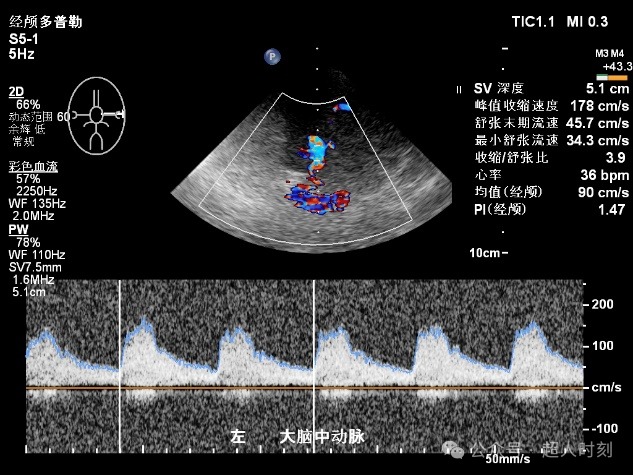

图5f 右大脑前动脉狭窄频谱(VP:263cm/s)